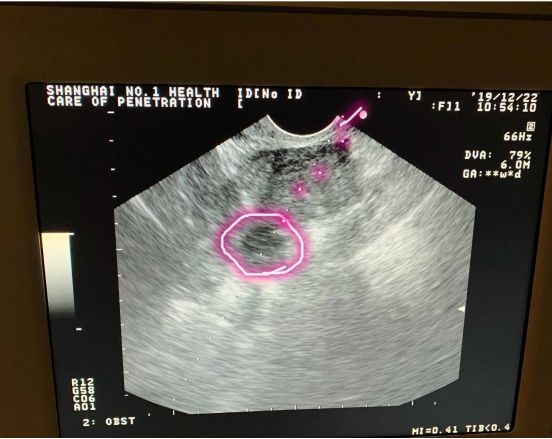

如果卵巢位置好,患者心理放松、对医生充分信任,再加上医生取卵技巧娴熟,那取卵过程会完全不痛或仅有轻微的痛感;反之,如果卵巢位置不好,在子宫后方,取卵针穿过子宫后才能穿刺到卵泡,那必定会有疼痛感的。

而这种情况,取卵针要经过子宫,长途跋涉后才能刺入卵泡,那肯定疼,我给你取卵也会疼!